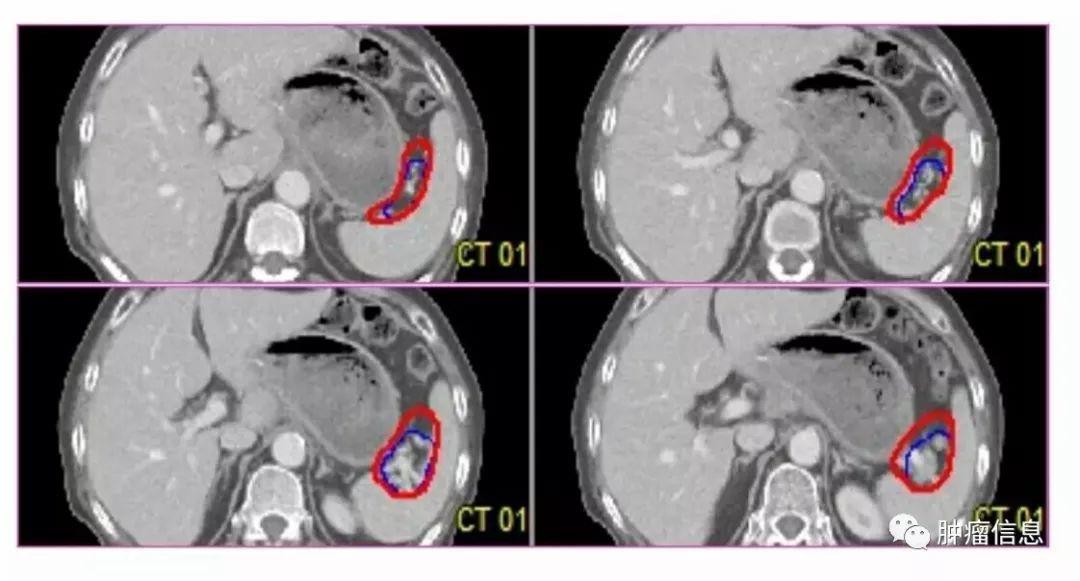

上腹部淋巴结分区范围及勾画

腹部淋巴结按UICC胃癌淋巴结分组分为1-16区:

贲门右淋巴结贲门左淋巴结胃小弯淋巴结胃大弯淋巴结(4sa:胃短血管淋巴结;4sb:胃网膜左血管淋巴结;4d:胃网膜右血管淋巴结)幽门上淋巴结幽门下淋巴结胃左动脉淋巴结肝总动脉淋巴结(8a:肝总动脉前淋巴结;8p:肝总动脉后淋巴结)腹腔干淋巴结脾门淋巴结脾动脉淋巴(11p:脾动脉近端淋巴结;11d:脾动脉远端淋巴结)肝十二指肠韧带淋巴结(12a:肝十二指肠韧带内沿肝动脉淋巴结;12b:肝十二指肠韧带内沿胆管淋巴结;12p:肝十二指肠韧带内沿门静脉后淋巴结)胰头后淋巴结肠系膜淋巴结(14v:肠系膜上静脉淋巴结;14a:肠系膜上动脉淋巴结)结肠中血管淋巴结腹主动脉旁淋巴结(16a1:主动脉裂孔淋巴结;16a2:腹腔干上缘至左肾静脉下缘之间腹主动脉周围淋巴结;16b1:左肾静脉下缘至肠系膜下动脉上缘之间腹主动脉周围淋巴结;16b2:肠系膜下动脉上缘至腹主动脉分叉之间腹主动脉周围淋巴结)

No.1-6胃周淋巴结

包括胃贲门左,贲门右,胃体左、胃体右、胃幽门左、胃幽门右